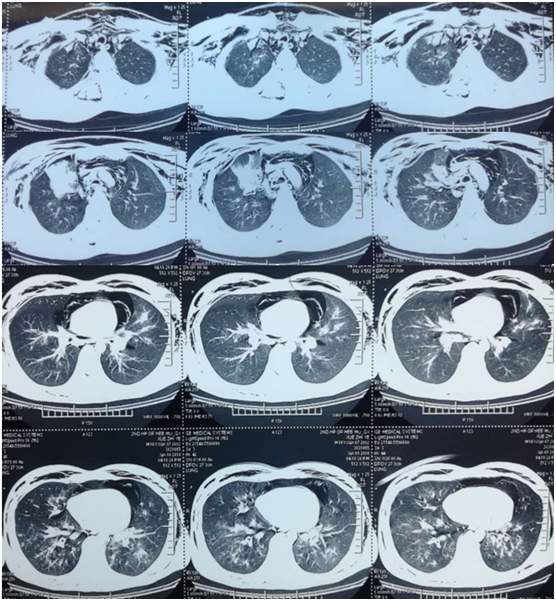

转入我科当天行胸部CT检查,距出现症状已2周余,与前相比进展快速,出现大片实变影,原有结节已融合,并且出现空洞。

图片